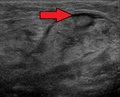

The submandibular gland accounts for 80% of all salivary duct calculi (salivary stones or sialolith), possibly due to the different nature of the saliva that it produces and the tortuous travel of the submandibular duct to its ductal opening for a considerable upward distance.[13] The submandibular gland is one of the major three glands that provide the mouth with saliva. The two other types of salivary glands are parotid and sublingual glands.[14]

- ^ Asai, S.; Okami, K.; Nakamura, N.; Shiraishi, S.; Yamashita, T.; Anar, D.; Matsushita, H.; Miyachi, H. (2012). "Sonographic appearance of the submandibular glands in patients with immunoglobulin G4-related disease". Journal of Ultrasound in Medicine. 31 (3): 489–493. doi:10.7863/jum.2012.31.3.489. PMID 22368140. S2CID 35940244.